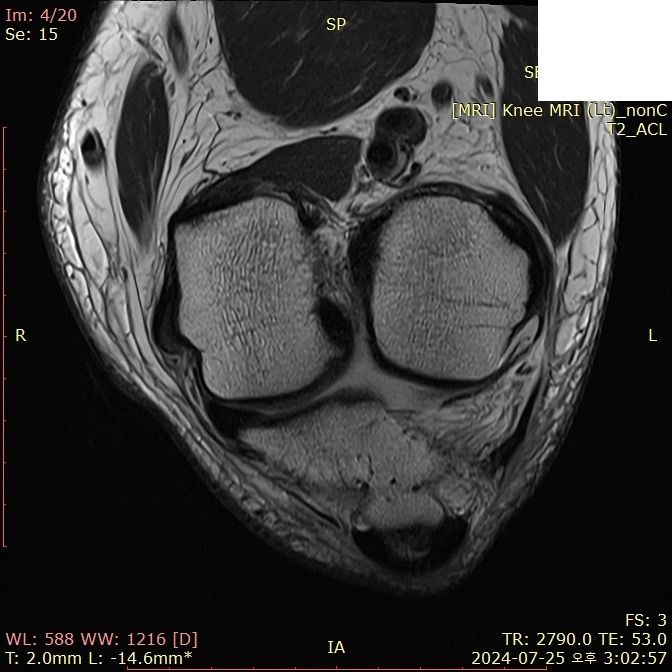

무릎 ACL(전방십자인대) 확인 부탁드려요

아스팔트에 무릎을 부딪쳐 심하게 부어서 mri 찍어봤는데 슬개골 비변위성 골절 판독 받은 건 기억 나는데, 인대는 기억이 잘 안나서 여쭤 봅니다..

전방십자인대 괜찮은가요...??ㅠㅠ